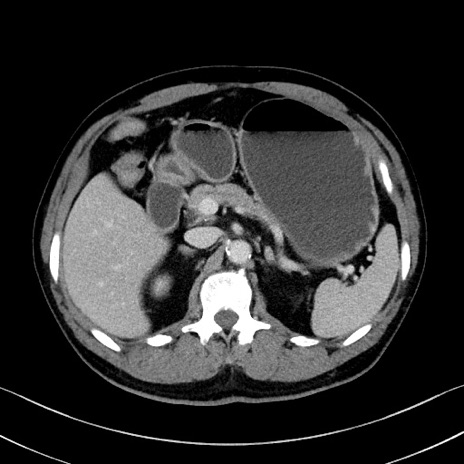

症例35(横断像)

【症例】70歳代 男性

【主訴】腹部膨満、嘔吐

【現病歴】昨日より腹部膨満感出現。本日増悪し、仙痛出現。嘔吐あり、受診。

【既往歴】糖尿病、胆摘後

【身体所見】BP 149/80mmHg、HR 74/min、BT 35.9℃、腹部:膨満、軟、圧痛なし。腸雑音減弱あり。上腹部正中切開瘢痕あり。

【データ】WBC 13500、CRP 1.72